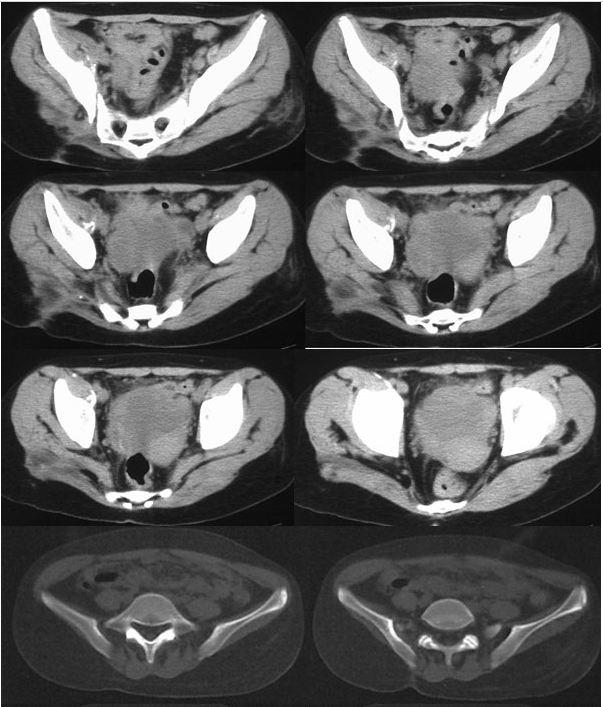

我的好友丹丹,老家有一个表妹,今年16岁,1年前无明显诱因出现右臀部酸痛,伴畏寒、发热、午后低热、盗汗,无双下肢放射痛,并出现左臀部皮肤红肿、破溃、流脓,曾在当地卫生院间断诊治,予以口服药物治疗,效果差,后逐渐出现右臀部外侧皮肤破溃、流脓,经自行口服药物后窦道自行愈合后,周围再次出现流脓,经久不愈,时有脓液流出。丹丹前两天回到老家,把表妹接到我院住院治疗。骨科专科检查发现右臀部一个约0.5x0 5 cm大小窦道口,按压周围可见黄色干酪样分泌物流出,局部可见肉芽组织,无红肿,周围可见多个窦道口疤痕。胸部X线检查:右上.中肺野及左中肺野可见片状.斑片(点)状.条索状阴影,边缘清晰,密度均匀。骨盆CT检查:右侧骶髂关节面骨质破坏、硬化,正常关节结构破坏,臀部软组织内可见囊性密度不均之肿块,影像诊断:右上.中肺.左中肺结核,右侧骶髂关节结核伴髂内肌冷脓肿形成、关节半脱位。

骶髂关节结核常见影像学表现为骨质破坏,死骨形成,关节间隙增宽或变窄,周围脓肿形成,部分伴有窦道。骨盆的X线平片检查可明显的看出骨质的改变,部分脓肿,但由于解剖结构的特殊性,无法显示全部的关节间隙。CT的密度分辨率较高,能够清晰的显示骨破坏程度、部位以及范围,对死骨、脓肿的形成及部位、窦道、囊肿等能够直观的检查,可以发现到X线检查难以观测的生理性骨化和病理性改变。

骶髂关节结核影像学表现:滑膜型结核早期关节囊肿胀,关节间隙增宽,继而侵及关节软骨和关节面;骨型结核早期在骶髂关节的骶骨或髂骨端见到孤立的圆形或椭圆形破坏区,边缘清楚,继而病变累及关节软骨和滑膜,导致关节边缘模糊、毛糙,骶髂关节前下部受累最早,且以髂骨侧破坏最严重。随着病变的进展,滑膜被增生的肉芽组织替代,干酪样坏死物聚集、侵蚀,死骨形成,最终使全关节受累,韧带软化、松弛,关节间隙增宽,这有别于其他大关节。由于骶髂关节结核的骨质疏松常不如其他关节明显,而往往显示有骨质增生硬化征象。关节破坏严重者,可造成病理性半脱位。大多有冷脓肿形成,多发生在臀部,有时在腹股沟、髂窝区,当脓肿增大,张力增高时,常自行破溃并沿着薄弱的组织间隙蔓延形成窦道。

(2)滑膜型骶髂关节结核呈:①关节面模糊、破坏,骨质破坏,关节间隙狭窄或不规则增宽;②大块死骨或散在颗粒状高密度影;③骨质增生硬化。

Ⅳ型:关节明显破坏,脓肿形成,部分关节半脱位,并累及椎体。